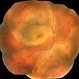

- acute posterior placoid chorioretinitis, acute syphilitic posterior placoid chorioretinitis

- An OCT image BE of 36 year old female showing RPE granularity and IS/OS irregularity in a case of syphilitic posterior placoid chorioretinitis